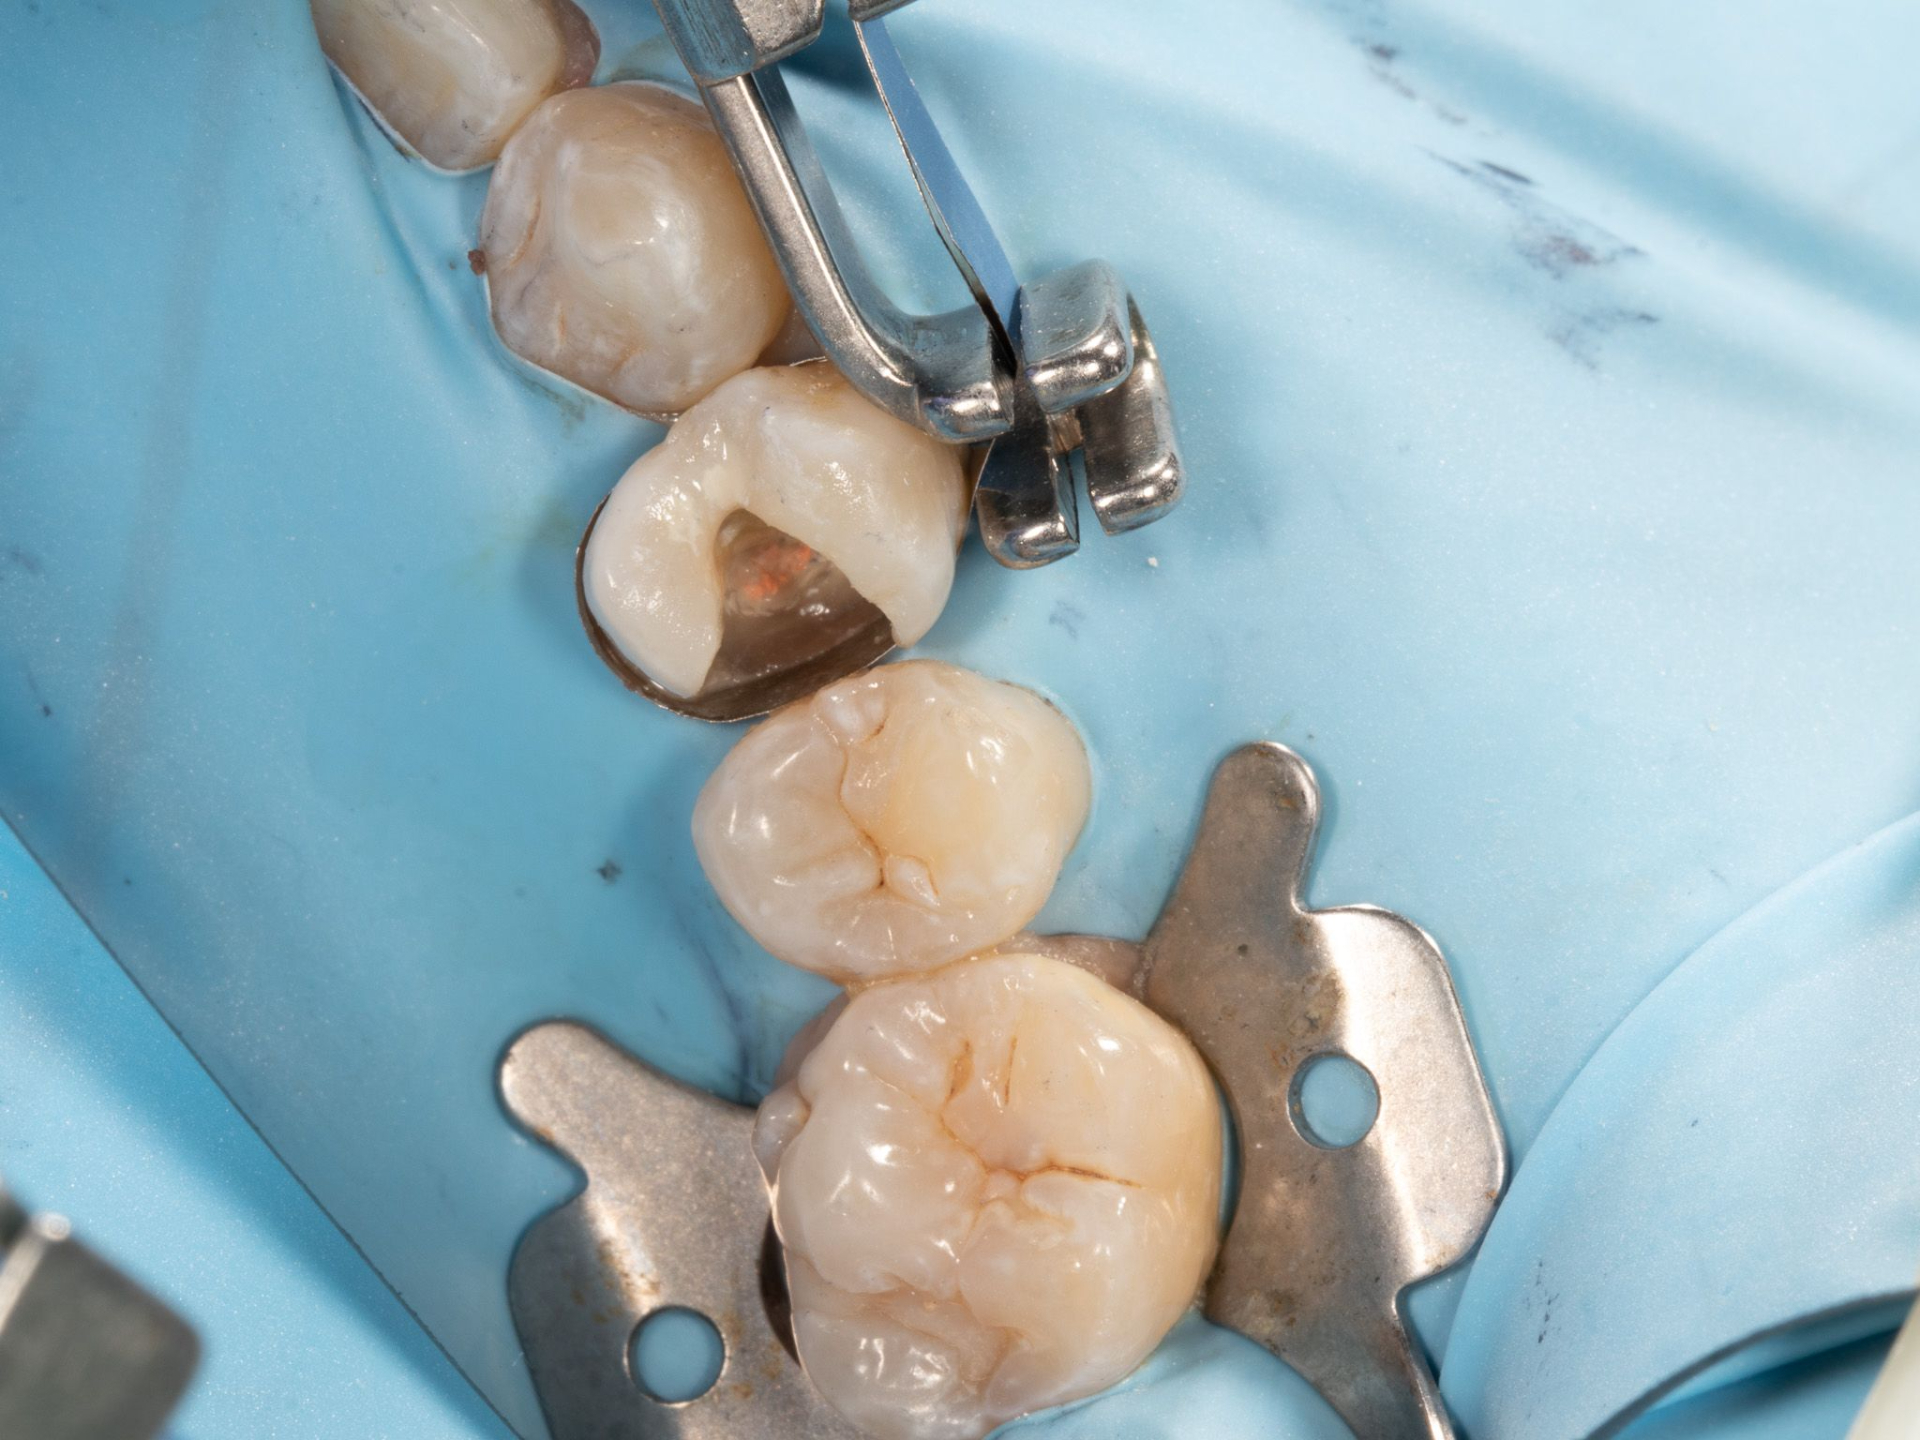

Course Description: This one-hour webinar, led by Dr. Melissa Seibert, DMD, MS, ABGD, explores minimally invasive techniques for caries removal. Participants will review the latest literature supporting selective caries removal, gain an in-depth understanding of caries etiology, and learn strategies to minimize the risk of pulp exposure. This evidence-based course emphasizes preserving tooth vitality while effectively managing carious lesions.

Discover the evidence-based principles behind the selective caries removal approach.

Understand the principles and rationale for selective caries removal.

Review the etiology and progression of dental caries.

Learn techniques to minimize the risk of pulp exposure during caries removal.

Explore evidence-based strategies for maintaining tooth vitality.